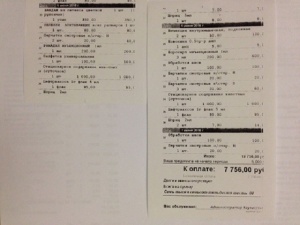

– салфетка стерильная марлевая 16 см х 14 см (33,95 руб.), салфетка стерильная марлевая 45 см х 29 см 4 шт. (155,20 руб.), бинт стерильный 7м х 14 см 7 шт. (169,75 руб.), хлоргексидина биглюконат раствор водный х 10 шт. (88,75 руб.) согласно листу назначений от 04.06.2016 (чек, товарный чек 2) - 447,65 руб.;

– окончательная оплата за проведение компьютерной томографии правого скакательного сустава (КТ) врач Горшков Сергей Сергеевич, и операции (снятие пластины) хирург Козлов Евгений Матвеевич, клиника Бэст (чек 3, товарный чек 3, лист назначений – документ 3) – 7756 руб.;

– салфетка стерильная марлевая 16 см х 14 см (33,95 руб.), салфетка стерильная марлевая 45 см х 29 см 4 шт. (155,20 руб.), бинт стерильный 7м х 14 см 7 шт. (169,75 руб.), хлоргексидина биглюконат раствор водный х 10 шт. (88,75 руб.) согласно листу назначений от 04.06.2016 (чек, товарный чек 2) - 447,65 руб.;

– окончательная оплата за проведение компьютерной томографии правого скакательного сустава (КТ) врач Горшков Сергей Сергеевич, и операции (снятие пластины) хирург Козлов Евгений Матвеевич, клиника Бэст (чек 3, товарный чек 3, лист назначений – документ 3) – 7756 руб.;

Лист приема и назначений от 15.06.2016, итоговый чек за период 02.03.2016 - 07.06.2016.

– оплата приема от 15.06.2016 и от 01.07.2016 хирург Козлов Евгений Матвеевич, клиника Бэст (чек 1, листы назначений – документ 1 и документ 2) – 650 руб.;

– оплата приема от 15.06.2016 и от 01.07.2016 хирург Козлов Евгений Матвеевич, клиника Бэст (чек 1, листы назначений – документ 1 и документ 2) – 650 руб.;